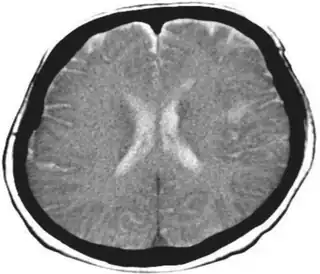

Stroke in left parietal lobe ( Gerstmann syndrome affected individual)

Diagnosis may be clinical if associated with dementia and other etiologies. In cases caused by stroke, MRI will show a corresponding stroke in the inferior parietal lobule. In the acute stage, this will be bright (restricted diffusion) on the DWI sequence and dark at the corresponding area on the ADC sequence.